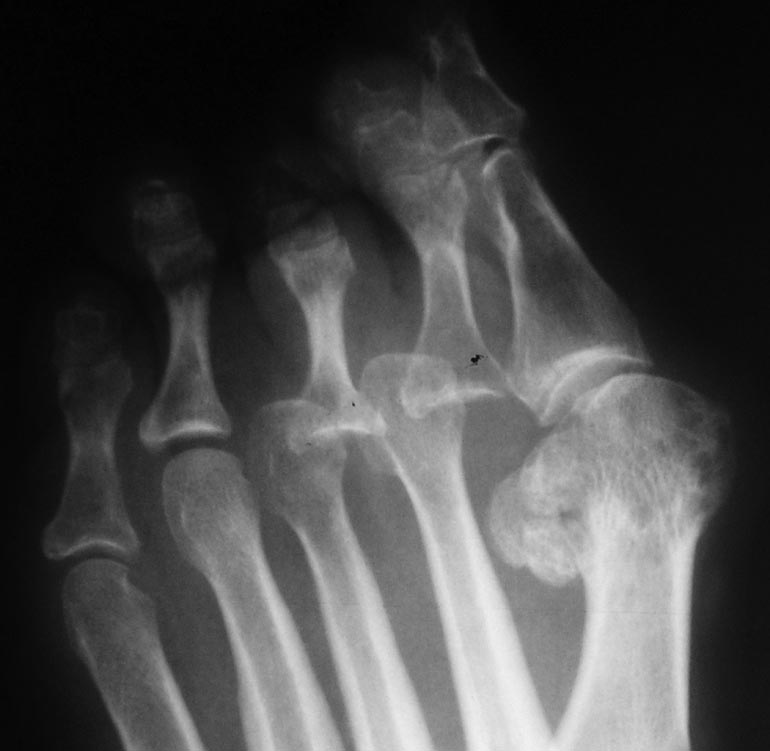

Нефиксированный Вейль значит без фиксации винтами. Заживает по тем же принципам, что и субкапитальные остеотомии в чрескожной хирургии, которые под воздействием ранней нагрузки (обувь с разгрузкой переднего отдела стопы здесь не нужна) находят свое идеальное положение. Только нужно учитывать, что рентгенологическое сращение может больше времени занять и не пугаться этого. На рентгенограммах пример такого Вейля 7-летней давности. Формула, конечно, не соблюдена, но вывихи вправлены без резекций головок.Поскольку уже давно такие операции делаю чрескожно, более свежих примеров нет.